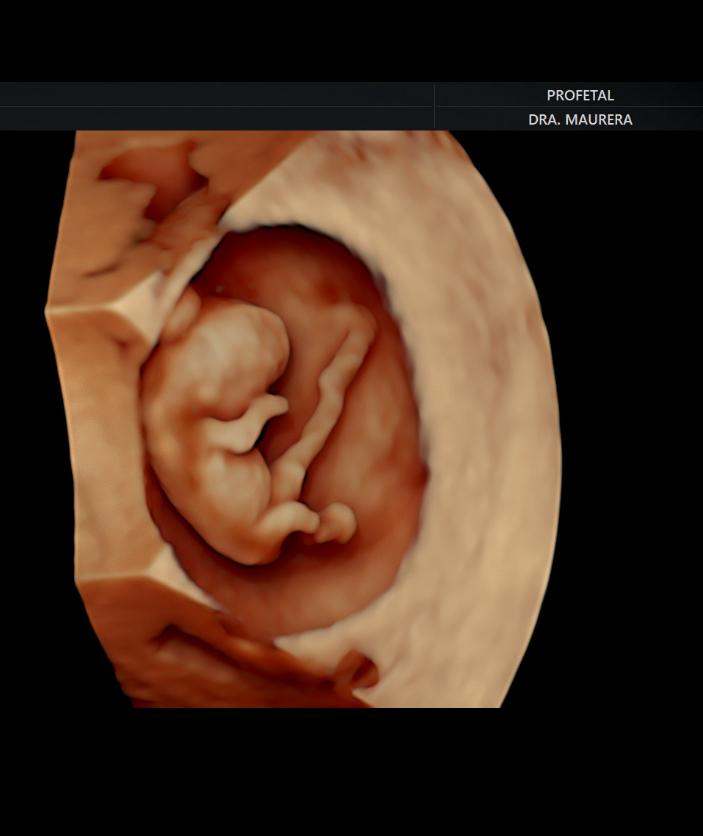

Entre los estudios ecográficos que ofrece se encuentran:

• Ecografía de Viabilidad (Semanas 4-11): Un examen transvaginal para confirmar la progresión normal del embarazo y el número de embriones. Es crucial para mujeres con sangrado, dolor, o antecedentes de abortos y embarazos ectópicos.

• Ecografía Genética Doppler (Semanas 12-14): Permite fijar la edad gestacional, diagnosticar embarazos múltiples y anomalías fetales, y evaluar el riesgo de Síndrome de Down, preeclampsia y parto prematuro.

• Ecografía Morfológica Doppler (Semanas 16-26): Un estudio detallado de cada parte del cuerpo fetal (cerebro, corazón, columna, órganos y extremidades) para descartar anomalías estructurales.